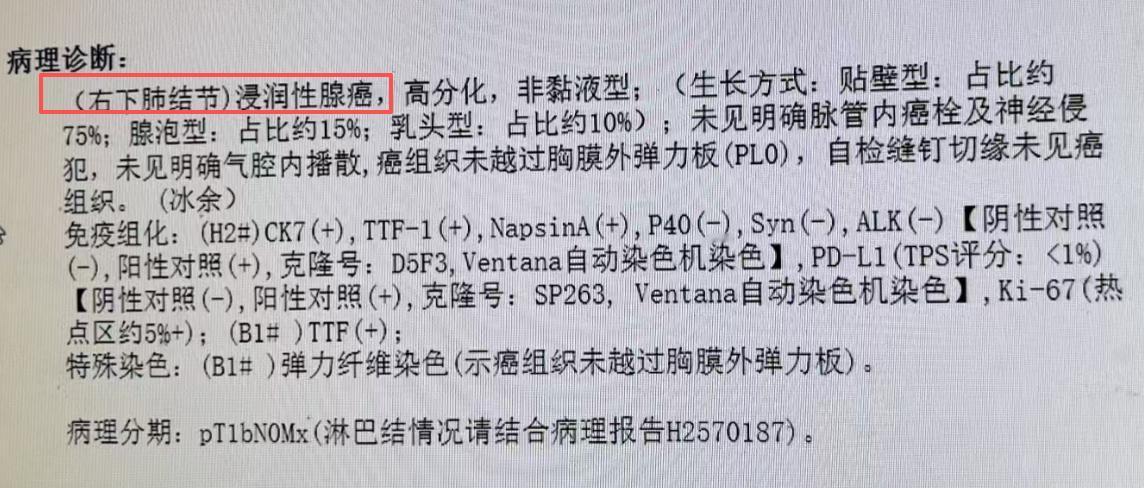

我的同行,一位 75 岁的医务工作者,6年前体检偶然查出的肺病灶,之后便一直处于观察状态。期间,大家普遍认为这只是肺大泡或肺气肿,并未过多警惕。 直到大概 4 年前,情况有了转折!当时他的太太因肺结节被确诊为早期肺癌,我为他太太主刀手术时,顺便仔细查看了他的肺部影像,当即提出一个不同的判断:这很可能是囊腔型肺癌,而非此前认为的良性病变。 今年,他再次复查,结果显示病灶较 2019 年明显增大 ——2019 年时病灶仅 1 公分,如今已长到两点几公分。 结合影像特征和病情进展,我判断早期肺癌的可能性极大,因此近期为他安排了手术。 其实,囊腔型肺癌近年来并不少见,仅这两个礼拜,我就接诊了十几例这类患者。很多人都会有疑问:为什么肺癌会呈现囊腔形态?囊腔型肺癌到底严重吗? 这里要跟大家说清楚:囊腔型肺癌的严重程度,关键看病灶内的软组织成分。如果软组织成分少,它的性质就类似原位癌或微浸润癌,恶性程度较低,预后也较好。 就像这位 75 岁的患者,虽然病灶体积增大了,但内部软组织成分很少,术后病理结果也证实是微浸润癌。 这类肺癌之所以会形成囊腔,核心原因是肿瘤细胞仅沿着肺泡壁生长,并不向外侵犯。在生长过程中,肿瘤细胞会产生一定张力,导致肺泡逐渐扩张,最终形成我们看到的囊腔形态。 之前还有病友特意打电话问我,说有人写文章说囊腔型肺癌很严重,为此十分担心。但事实上,大多数薄壁、软组织成分少的囊腔型肺癌,都属于早期病变,只要及时通过手术处理,术后通常不需要进行放化疗等后续治疗,治愈率很高。 当然,即便属于早期,一旦发现病灶有增大趋势,还是要尽早手术干预,避免病情进一步发展。[玫瑰][作揖]